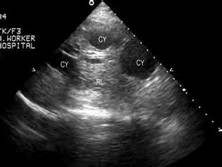

非寄生虫性肝囊肿是指肝内非寄生虫感染的浆液性囊肿,是一种较常见的先天性肝畸形,故又称为先天性肝囊肿。非寄生虫性肝囊肿绝大多数是肝脏的良性疾病。该病大多数病人无自觉症状,只有当囊肿大到一定程度才觉得偶有右上腹不适,或因上腹部突然发现一个无痛性包块而就医。

• 应该做哪些检查项目呢?腹部CT、肝胆B超、X线平片、放射性核素检查